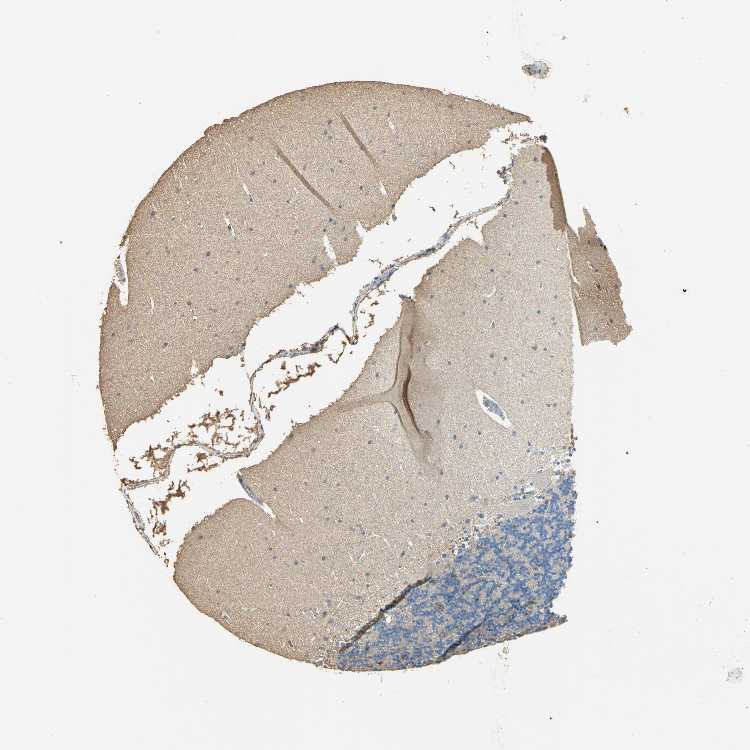

CEREBELLUM - Antibody stainingi

Antibody staining in the annotated cell types in the current human tissue is reported as not detected, low, medium, or high, based on conventional immunohistochemistry profiling in selected tissues. This score is based on the combination of the staining intensity and fraction of stained cells.

Each image is clickable and will lead to virtual microscopy that enables deeper exploration of all samples and also displays staining intensity scores, fraction scores and subcellular localization as well as patient and tissue information for each sample.

Antibody HPA040067Antibody HPA061280Antibody CAB005197Antibody CAB016392Antibody CAB079968

Purkinje cells Not detectedNot detectedLowNot detectedNot detected

Cells in granular layer LowNot detectedNot detectedLowNot detected

Cells in molecular layer Not detectedLowNot detectedMediumNot detected